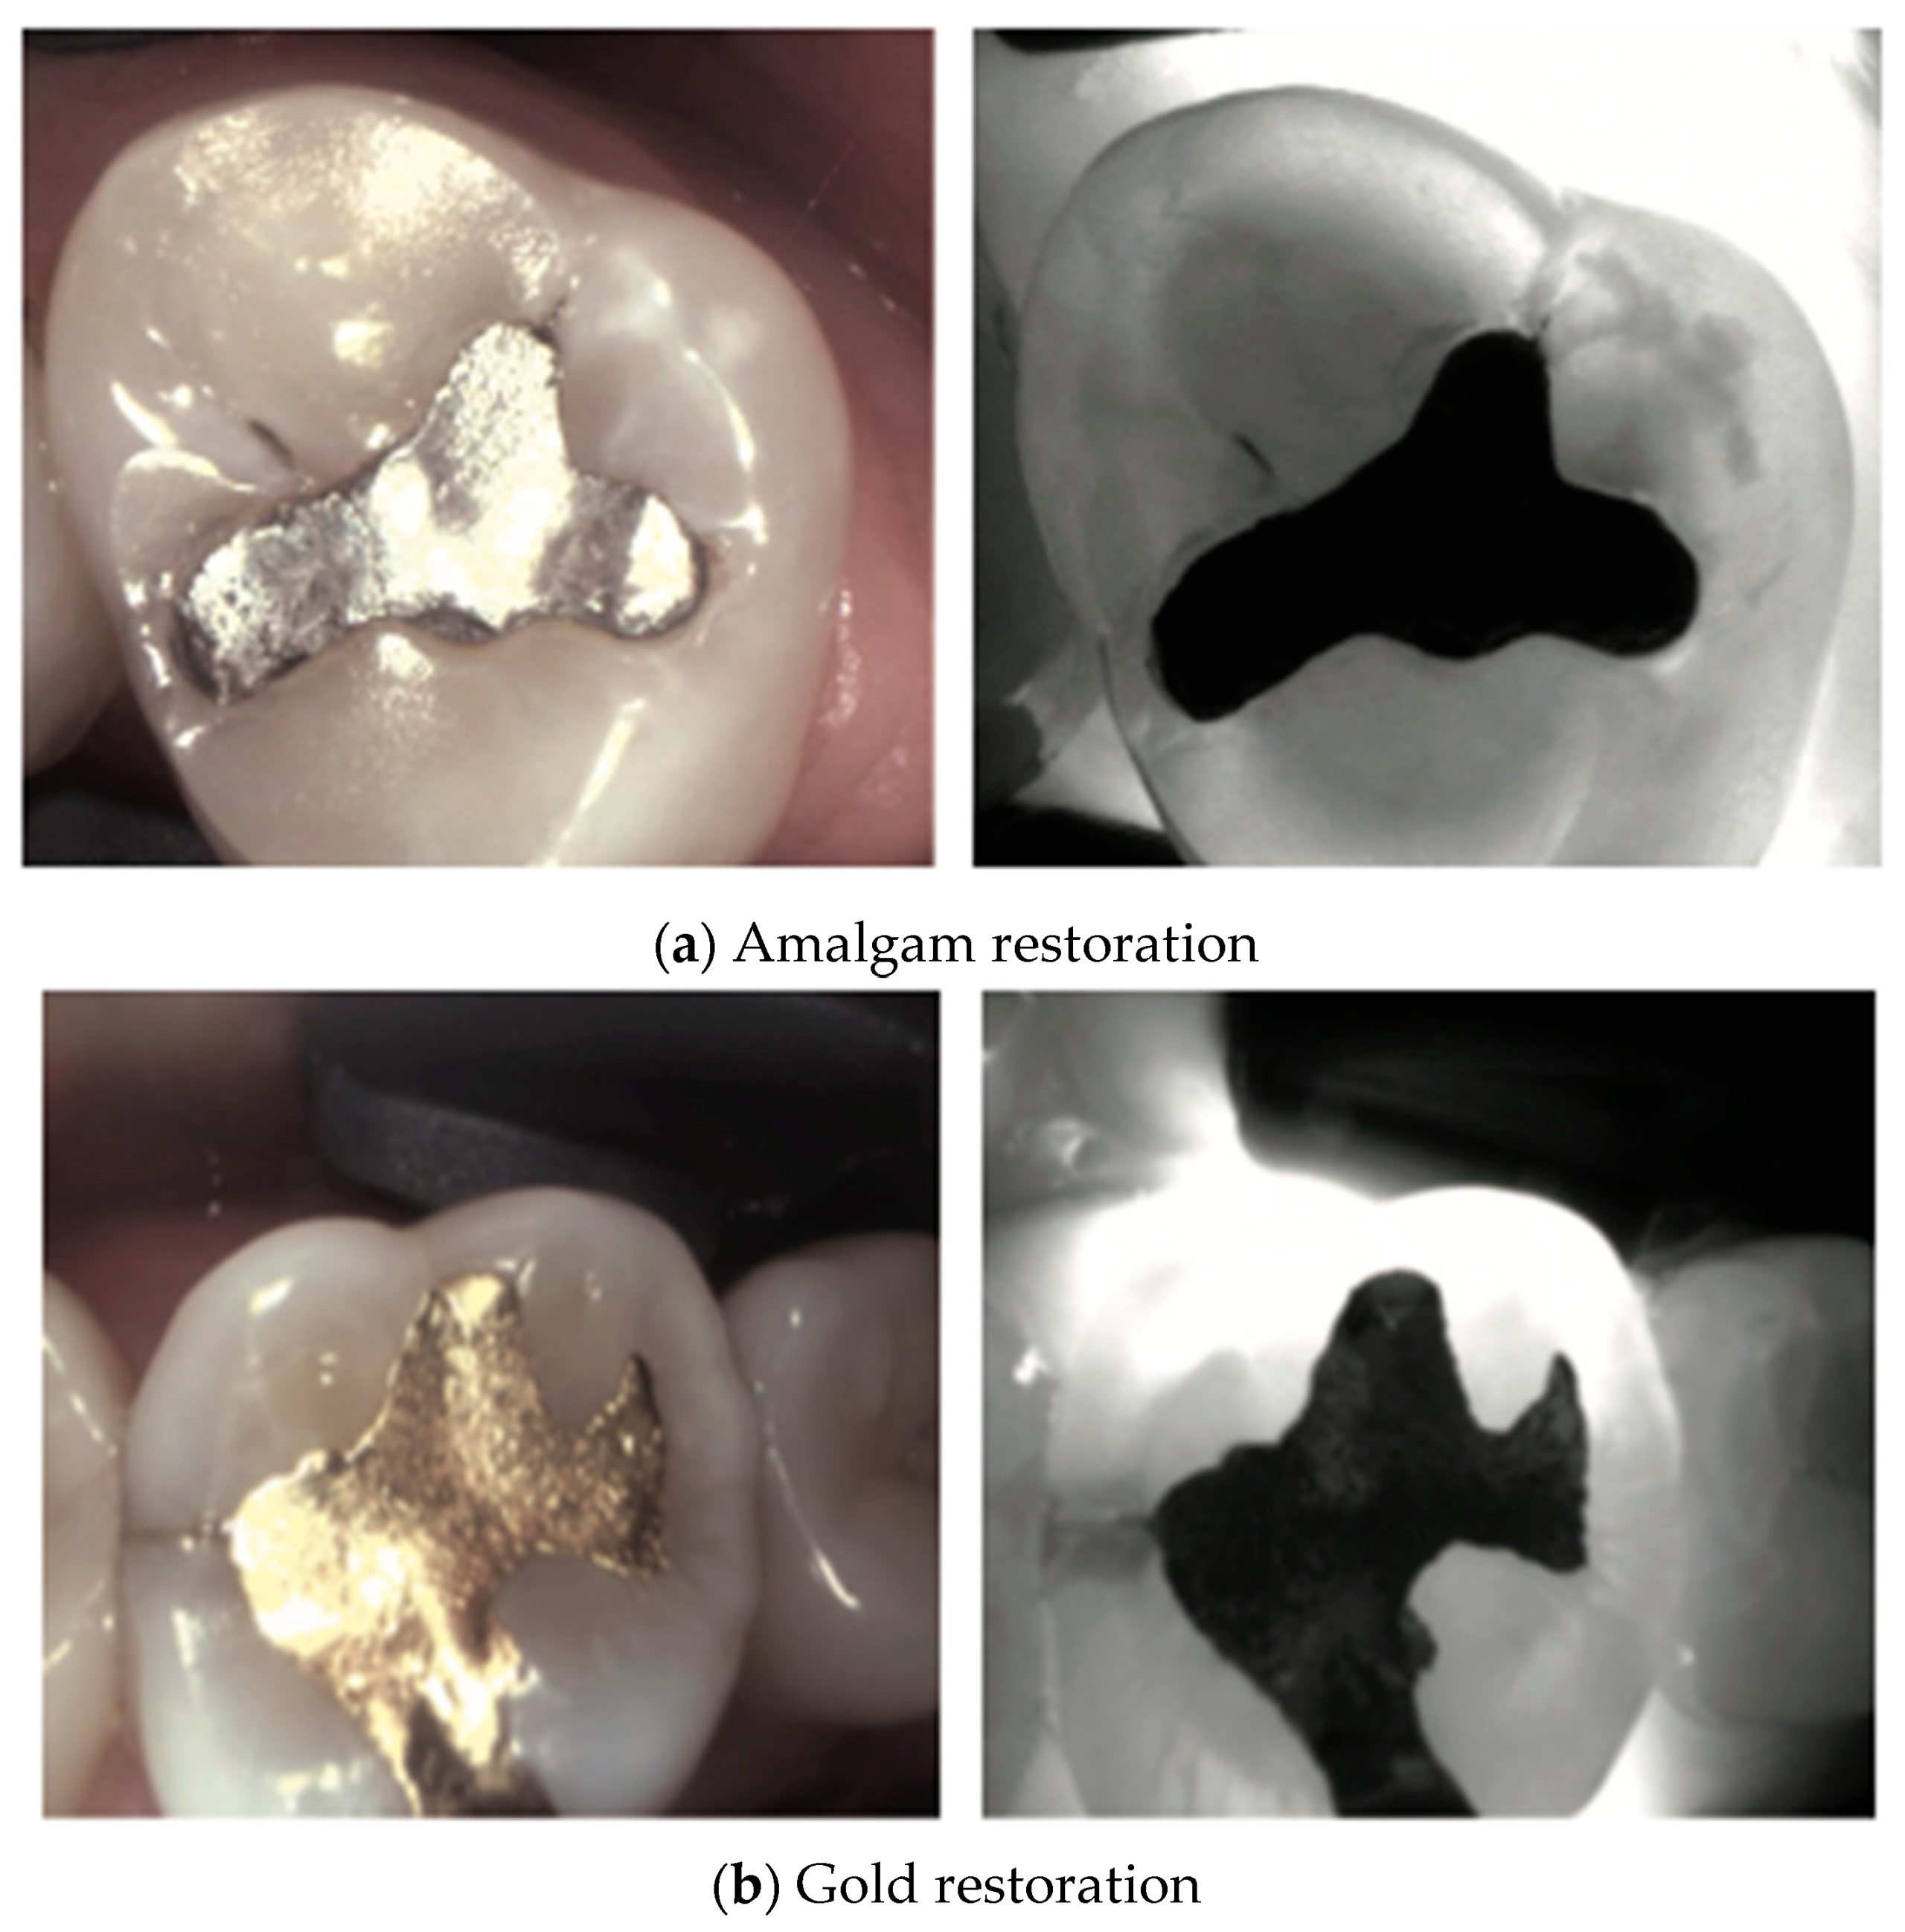

2. Carious Teeth

3. Restored Teeth